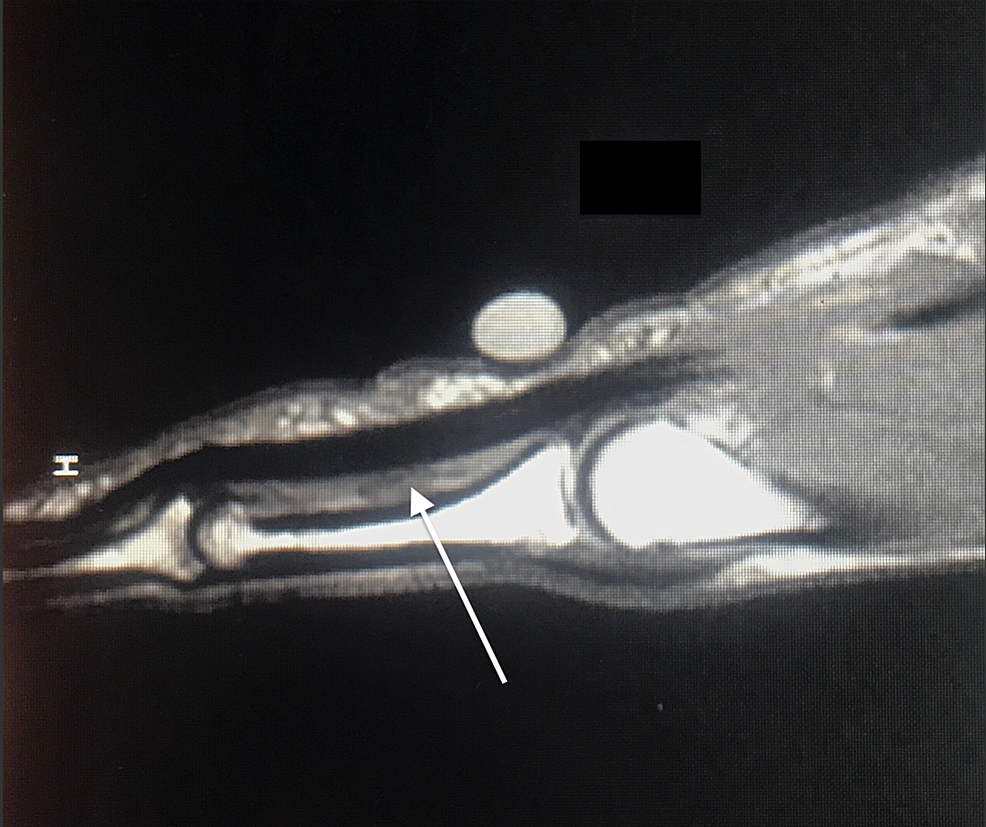

(A) Longitudinal view of A2 pulley rupture, volar displacement of... Download Scientific Diagram Torn A2 Pulley    an injury to the a2 pulley could be as simple as a mild strain, or as advanced as a complete rupture of the pulley. A4 is the most flexible. If multiple pulleys rupture, this may present with what is known as “bowstringing.” 5 to understand what bowstringing is, envision a bow (as in bow and arrow).  how do. Torn A2 Pulley.

(A) Longitudinal view of A2 pulley rupture, volar displacement of... Download Scientific Diagram Torn A2 Pulley    the most common signs of finger pulley injuries include:  the most common injury in climbers is the a2 pulley sprain or rupture and is caused by overloading the tissue. A4 rupture often seen with a3 rupture. Measuring the distance of bowstringing of the flexor tendons from the bone using ultrasound.  how do you diagnose and classify pull. Torn A2 Pulley.

Complete A2 Pulley Rupture Long view of the finger showing that the tendon (black, on the left Torn A2 Pulley  If multiple pulleys rupture, this may present with what is known as “bowstringing.” 5 to understand what bowstringing is, envision a bow (as in bow and arrow).   an injury to the a2 pulley could be as simple as a mild strain, or as advanced as a complete rupture of the pulley. Most commonly, either the middle or index digit. Torn A2 Pulley.